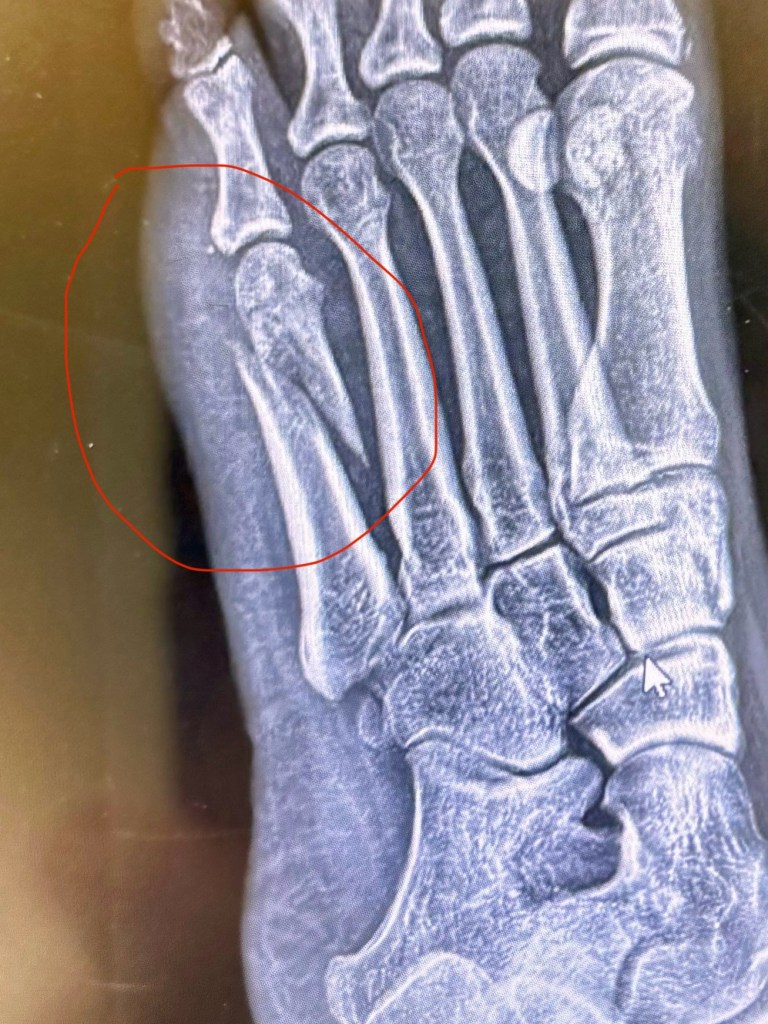

The break on my left foot, in the left metatarsal, is completely severed in two:

The Orthopedist told me that it’ll take several months to heal, and that it’s going to “suck” for a long time.

I have crutches and a cast shoe I’m supposed to wear, but the majority of the time, I do just fine with strategic foot placement when walking (hobbling). I can’t stand fully on my foot with it flat on the ground, yet- I have to keep the left side (surrounding the severed bone) uplifted from the ground, forcing the bulk of my weight onto my heel. It took some getting used to but I’m like Speedy Gonzalez now, zipping around the house and yard- cleaning, cooking, gardening, shopping, and everything else I want to do.